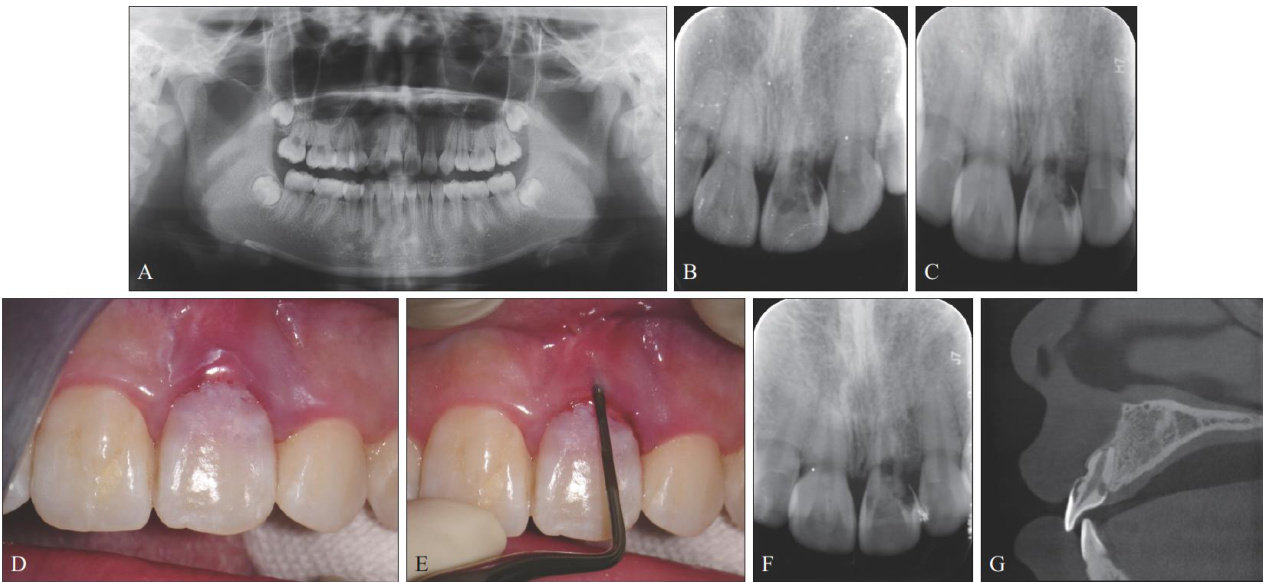

[摘要]牙吸收是在破牙细胞持续作用下发生的牙齿硬组织破坏。牙颈部外吸收是由于牙周膜或上皮下牙骨质破坏和(或)缺陷导致的牙齿颈部吸收。本文报道1例上颌中切牙外伤及正畸后牙颈部外吸收,术前通过锥形束CT充分了解患牙吸收部位和形态,术中利用显微技术及生物陶瓷和复合树脂材料分层修补对吸收部位进行严密充填修复,实现了保存患牙和尽可能长时间保存患牙健康牙髓的目标,术后6年随访效果良好。